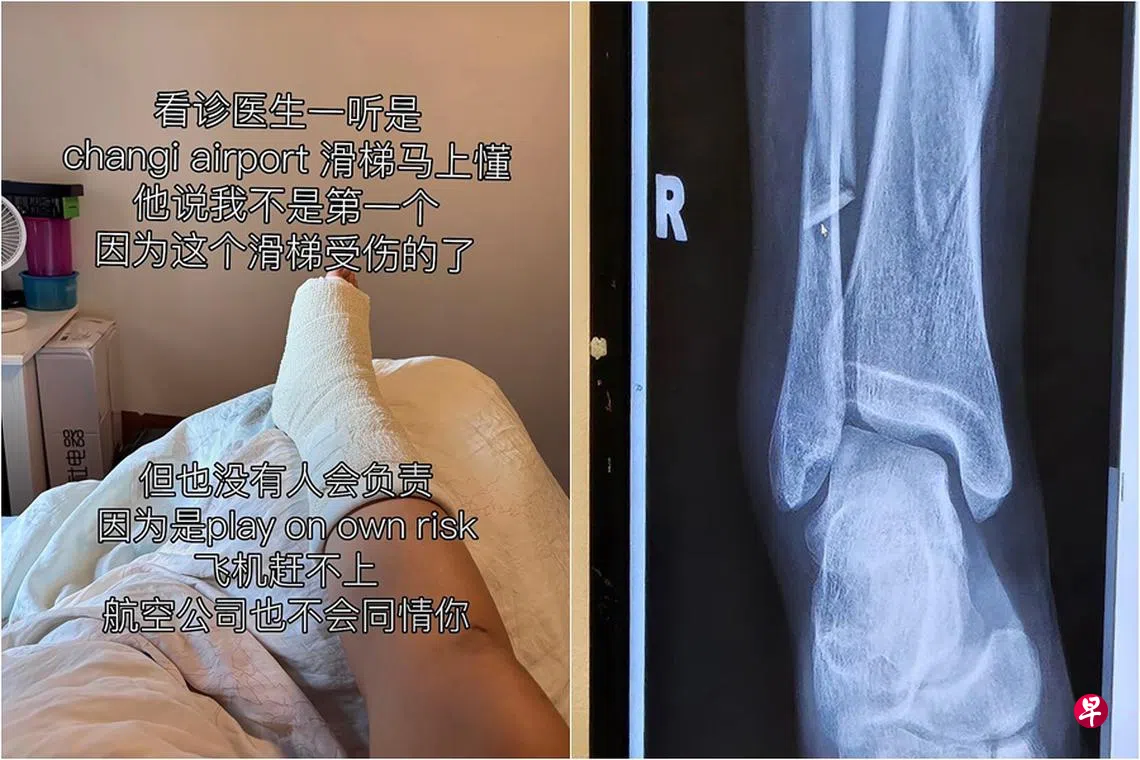

女游客在樟宜机场过境区玩滑梯,结果不慎腿骨折受伤入院,不仅错过航班回国,还得动手术植铁片。樟宜机场集团受询时促请公众遵守安全指南。

根据X光照片,女游客折断了右腿的一大一小两根腿骨。

她说,前后折腾六个小时才打好石膏,已近凌晨4时。借宿新加坡的亲戚家处理后续事宜,她第二天乘车离境,回到吉隆坡进一步治疗。

她目前须动手术植入铁片和螺丝固定骨折的腿骨,医药费预估4万令吉(约1万2000新元),外加之前在新加坡花费约500新元。